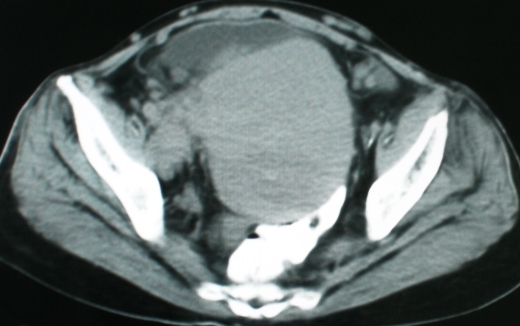

以下是引用zsl6918在2008-11-4 19:14:00的发言:[br]多发转移性改变,子宫改变不除外为原发灶